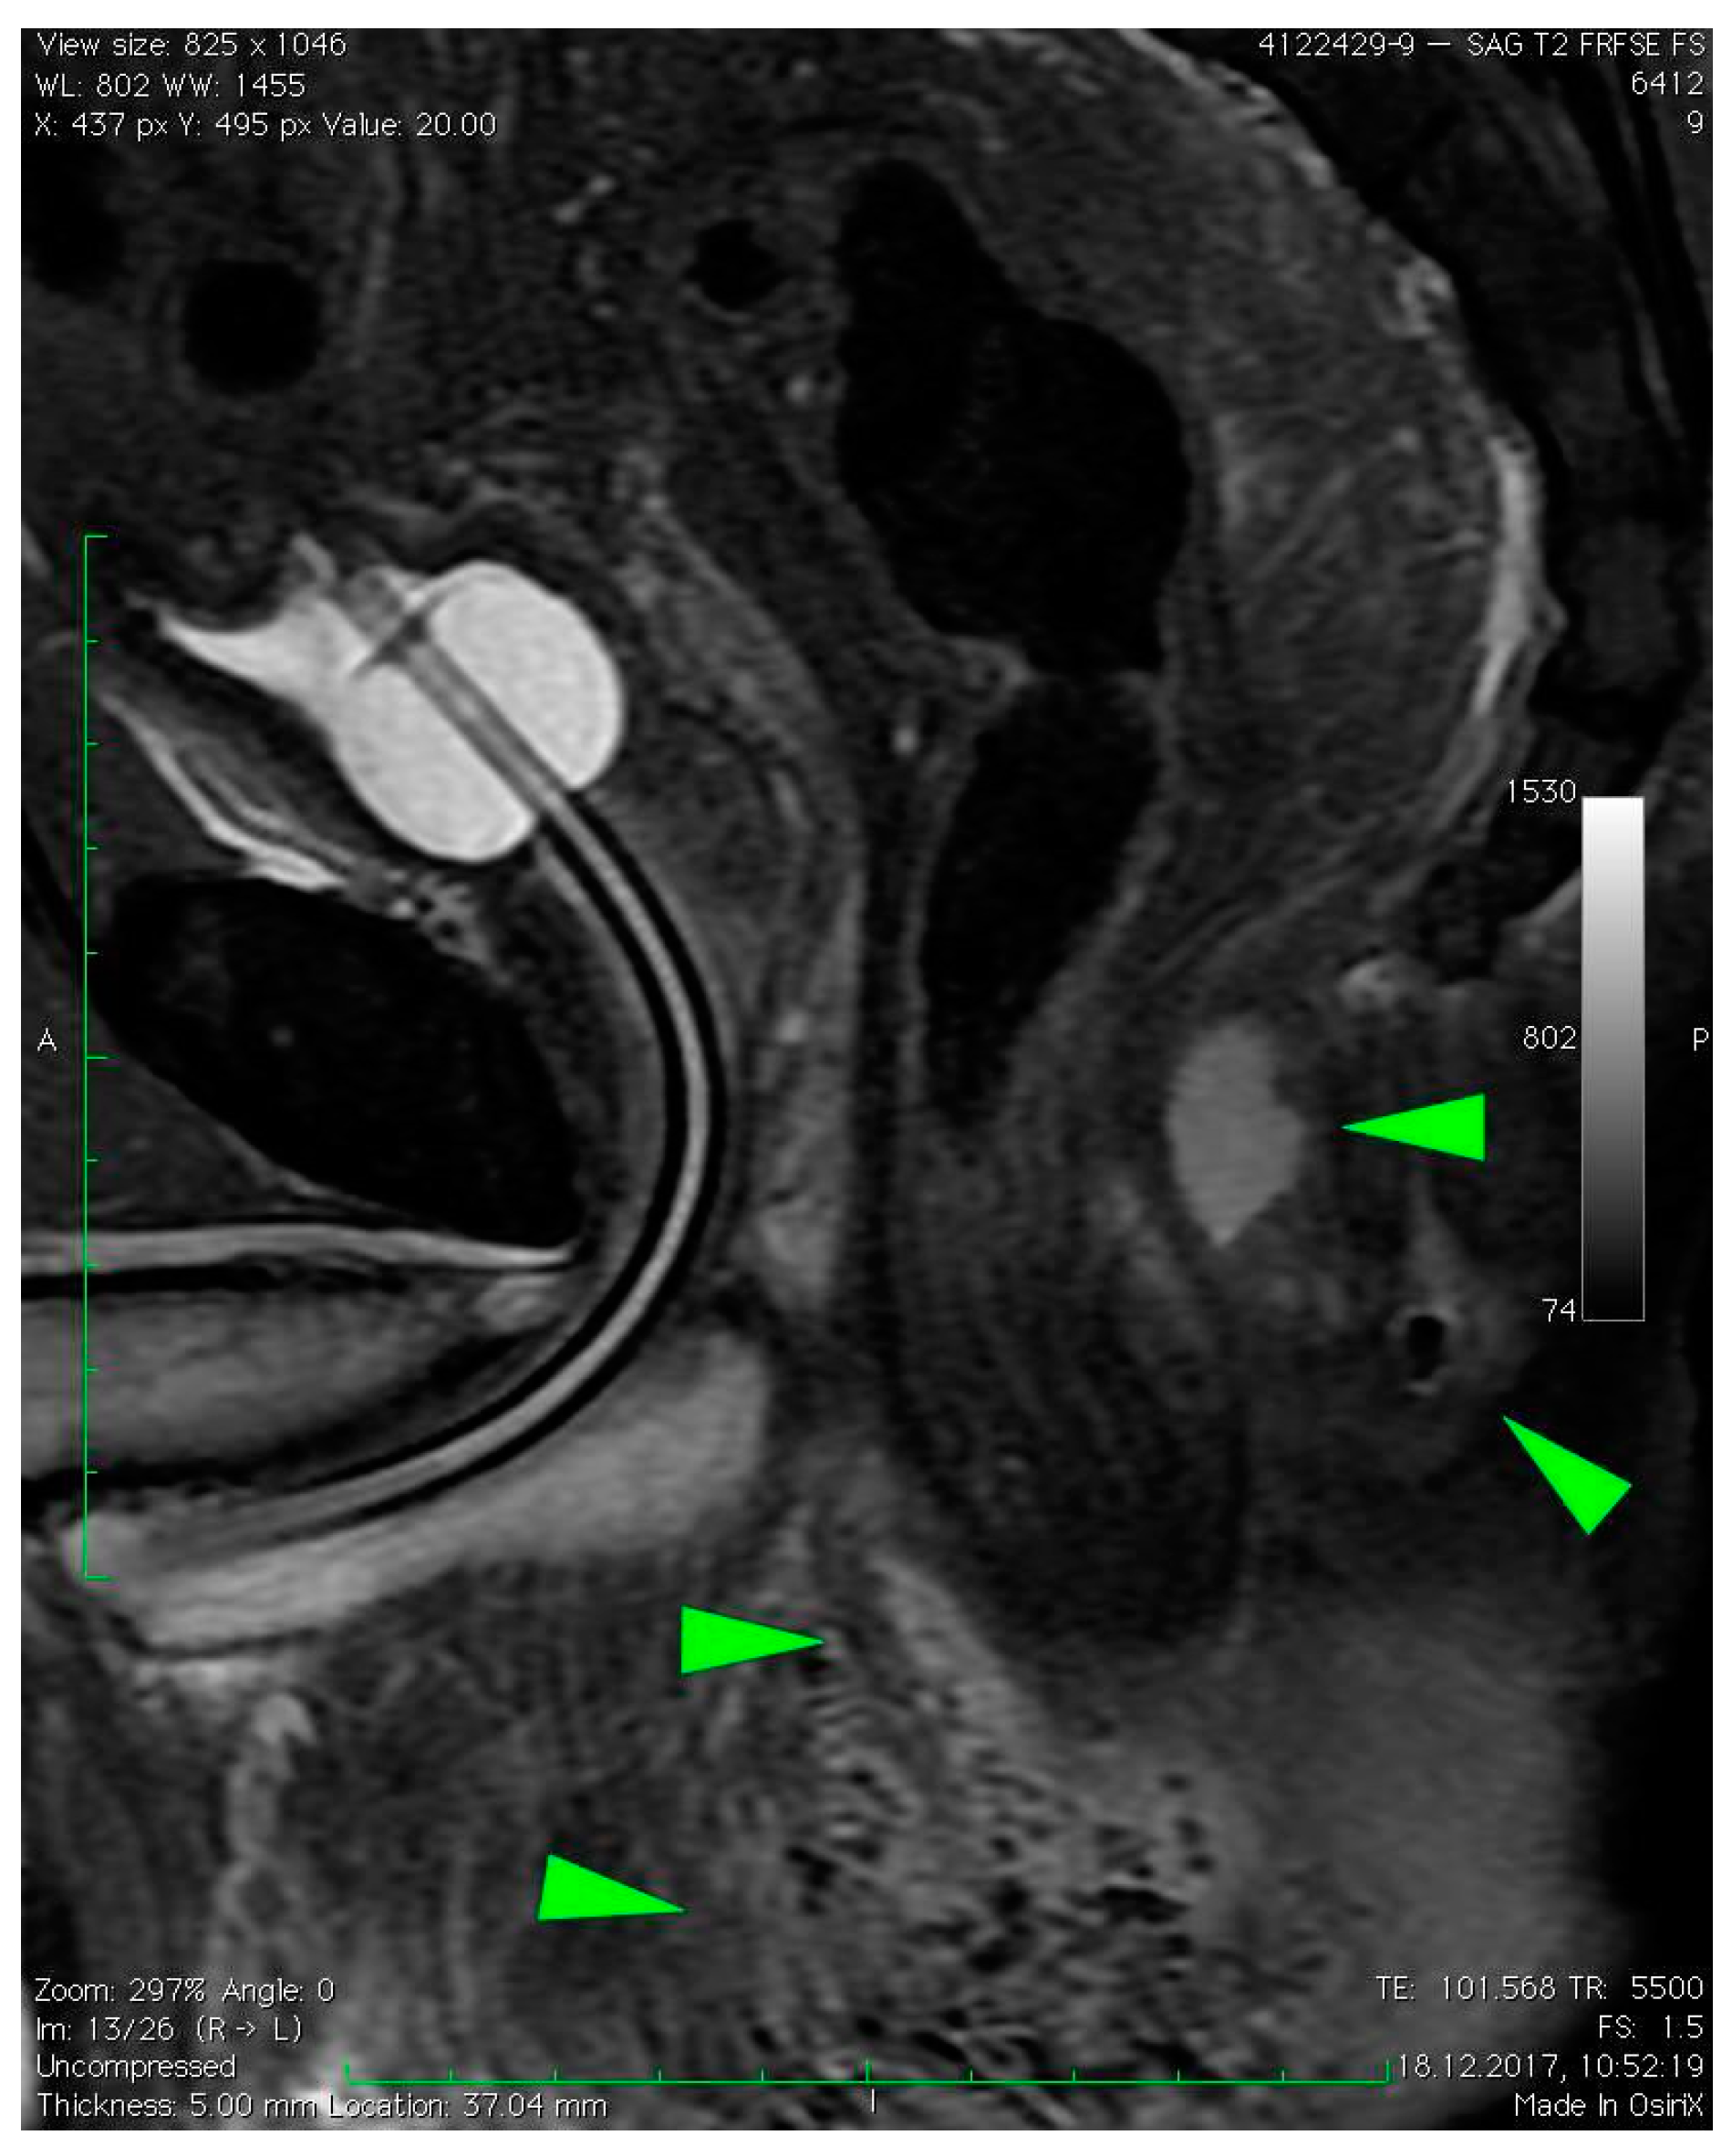

3. Case Presentation